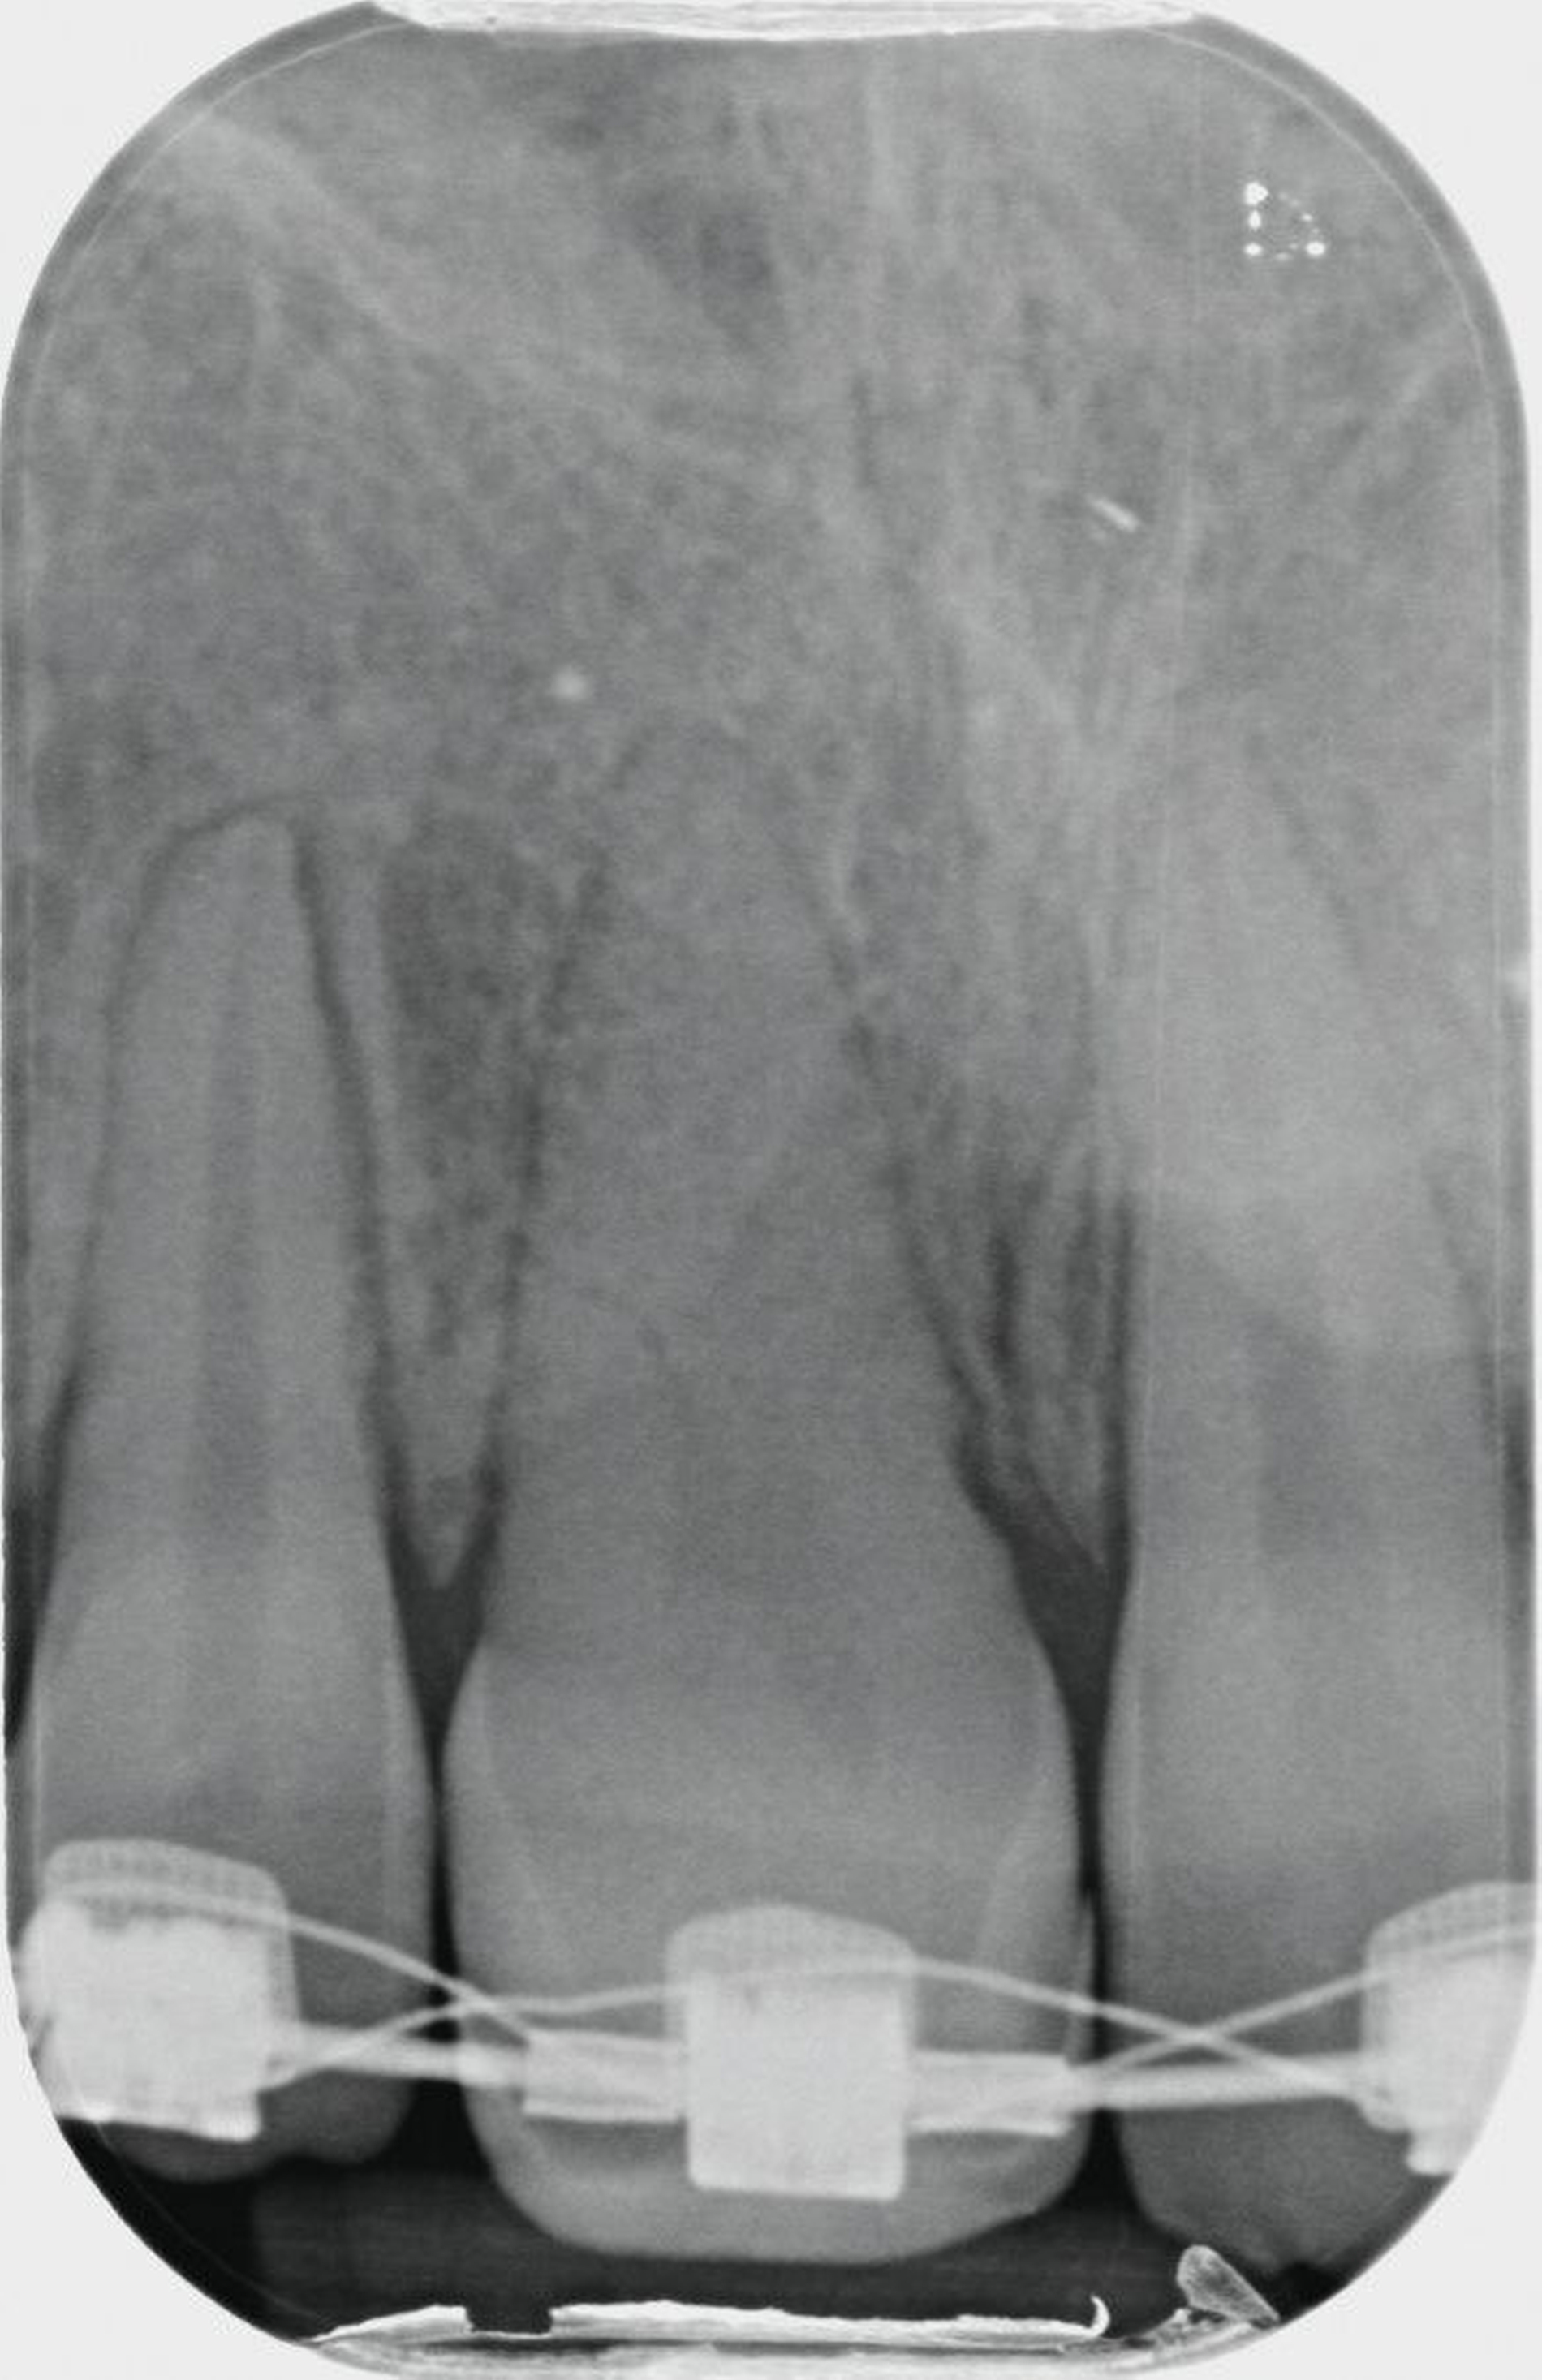

Im OPG findet sich nach Replantation mit Pulpotomie (Abbildung 2a) bereits ein vertikaler Einbruch des krestalen Knochens, drei Monate später ist eine infektionsbedingte Resorption des Zahnes 11 erkennbar (Abbildung 2b). Alle vier Milcheckzähne zeigen im Alter von neun Jahren bereits deutlich reduzierte Wurzellängen aufgrund der natürlichen Exfoliation durch die im Durchbruch befindlichen bleibenden Eckzähne. Die Entscheidung fiel auf den Zahn 83 als Autotransplantat, da dieser zu diesem Zeitpunkt die längste Wurzel aufwies (Abbildung 2b).

Im Alter von 13,2 Jahren – 4,2 Jahre nach der Milchzahn-TX – stellte sich die Patientin erneut in unserer Praxisklinik vor, um über die weiteren Therapiealternativen zu entscheiden. In enger Absprache mit der behandelnden Kieferorthopädin und den Eltern wurde die Prämolaren-Transplantation als weitere Therapie festgelegt. Auf Wunsch der Kieferorthopädin wurde aus gnathologischen Gründen der Zahn 25 als Transplantat gewählt.

Um störende okklusale Kontakte zu vermeiden, wurde der Zahn in eine leichte Infraposition gestellt und der Biss in der initialen Einheilphase von ein bis zwei Wochen leicht gesperrt, so dass die anschließende kieferorthopädische Extrusion des Zahnes ungestört durchgeführt werden konnte. Mit der kieferorthopädischen Bewegung und Feineinstellung des Transplantats wurde ab der vierten postoperativen Woche begonnen.

Durch die 90-Grad-Rotation des Transplantats stellt sich der Zahn anatomisch in der okklusalen Ansicht (Abbildung 7a) in der Sagittalen nahezu so breit dar wie der Nachbarzahn 21. Der adhäsive Frontzahnaufbau erfolgte drei Monate postoperativ noch unter der kieferorthopädischen Bracketierung. Die Weichgewebshöhe am Transplantat 11 ist durch die kieferorthopädische Extrusion ebenfalls als isogingival zum Nachbarzahn 21 zu erkennen. Der Klopfschall am TX-Zahn 11 war normoton und wies keine Ankylose auf. Die Sensibilitätsprüfung des Zahnes war positiv. Die Obliteration der Zahnwurzel weist auf eine vitale Reaktion des Pulpagewebes hin, wie man sie auch bei erfolgreich replantierten jugendlichen Zähnen beobachtet.